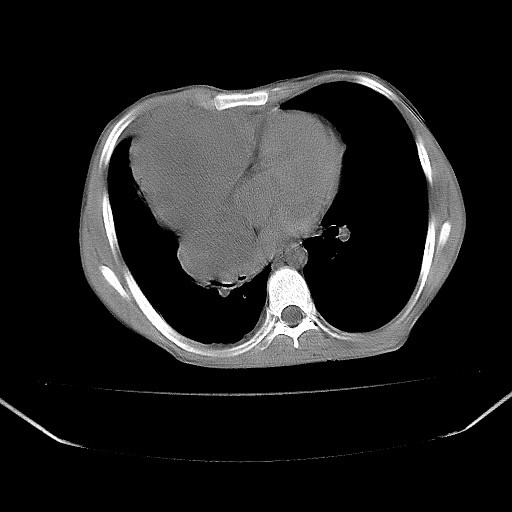

以下是引用zjzjr在2008-7-20 12:57:00的发言:[br]考虑为生殖源性肿瘤(内胚窦瘤),侵袭性胸腺瘤可能性大;右侧少量胸腔积液。

以下是引用xinliheng001在2008-7-20 21:17:00的发言:[br]右纵隔巨大分叶状软组织均质密度肿块,右上肺叶受压明显,纵隔右移、胸膜受累有少量积液和结节样增厚。应增强扫描一定会有更具诊断价值的信息。

以下是引用xinliheng001在2008-7-20 21:17:00的发言:[br]右纵隔巨大分叶状软组织均质密度肿块,右上肺叶受压明显,纵隔右移、胸膜受累有少量积液和结节样增厚。应增强扫描一定会有更具诊断价值的信息。